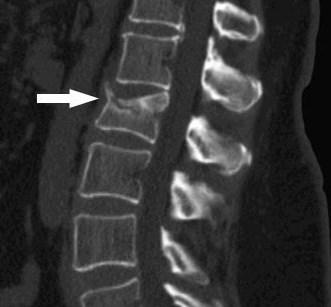

Tomografía computarizada de la columna vertebral

La tomografía computarizada de la columna es más detallada que la radiografía estándar

Una tomografía computarizada revela imágenes detalladas de cualquier parte del cuerpo, incluyendo los huesos, los músculos, la grasa y los órganos. Las tomografías computarizadas de la columna son más detalladas que las radiografías estándar.

Con este procedimiento se puede lograr información más detallada sobre las vértebras y tejidos espinales, obteniendo más información relacionada con lesiones y / o enfermedades de la columna vertebral.